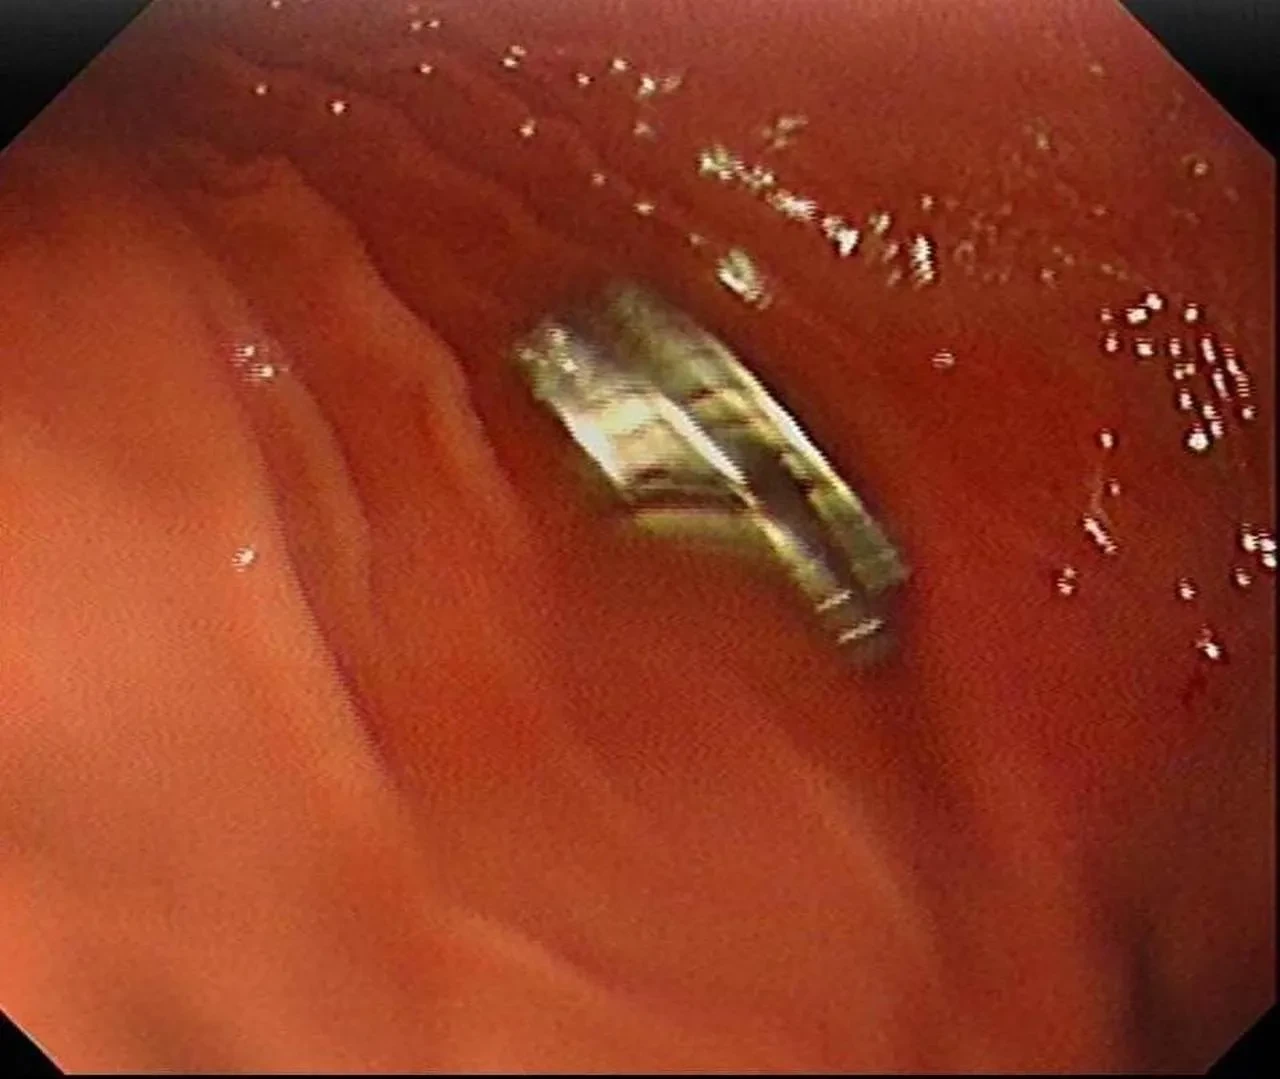

Elazığ'da 3 yaşındaki bir çocuğun yuttuğu 19 mıknatıs başarılı bir operasyonla çıkarıldı.

Fırat Üniversitesi Hastanesi'nde endoskopik yöntemle mıknatıslar çıkarıldı. Mıknatıslar yemek borusuna zarar verdi.

Çocuğun sağlık durumu iyi ve taburcu edildi. Operasyon sonrası çocuğun durumu stabil hale geldi.